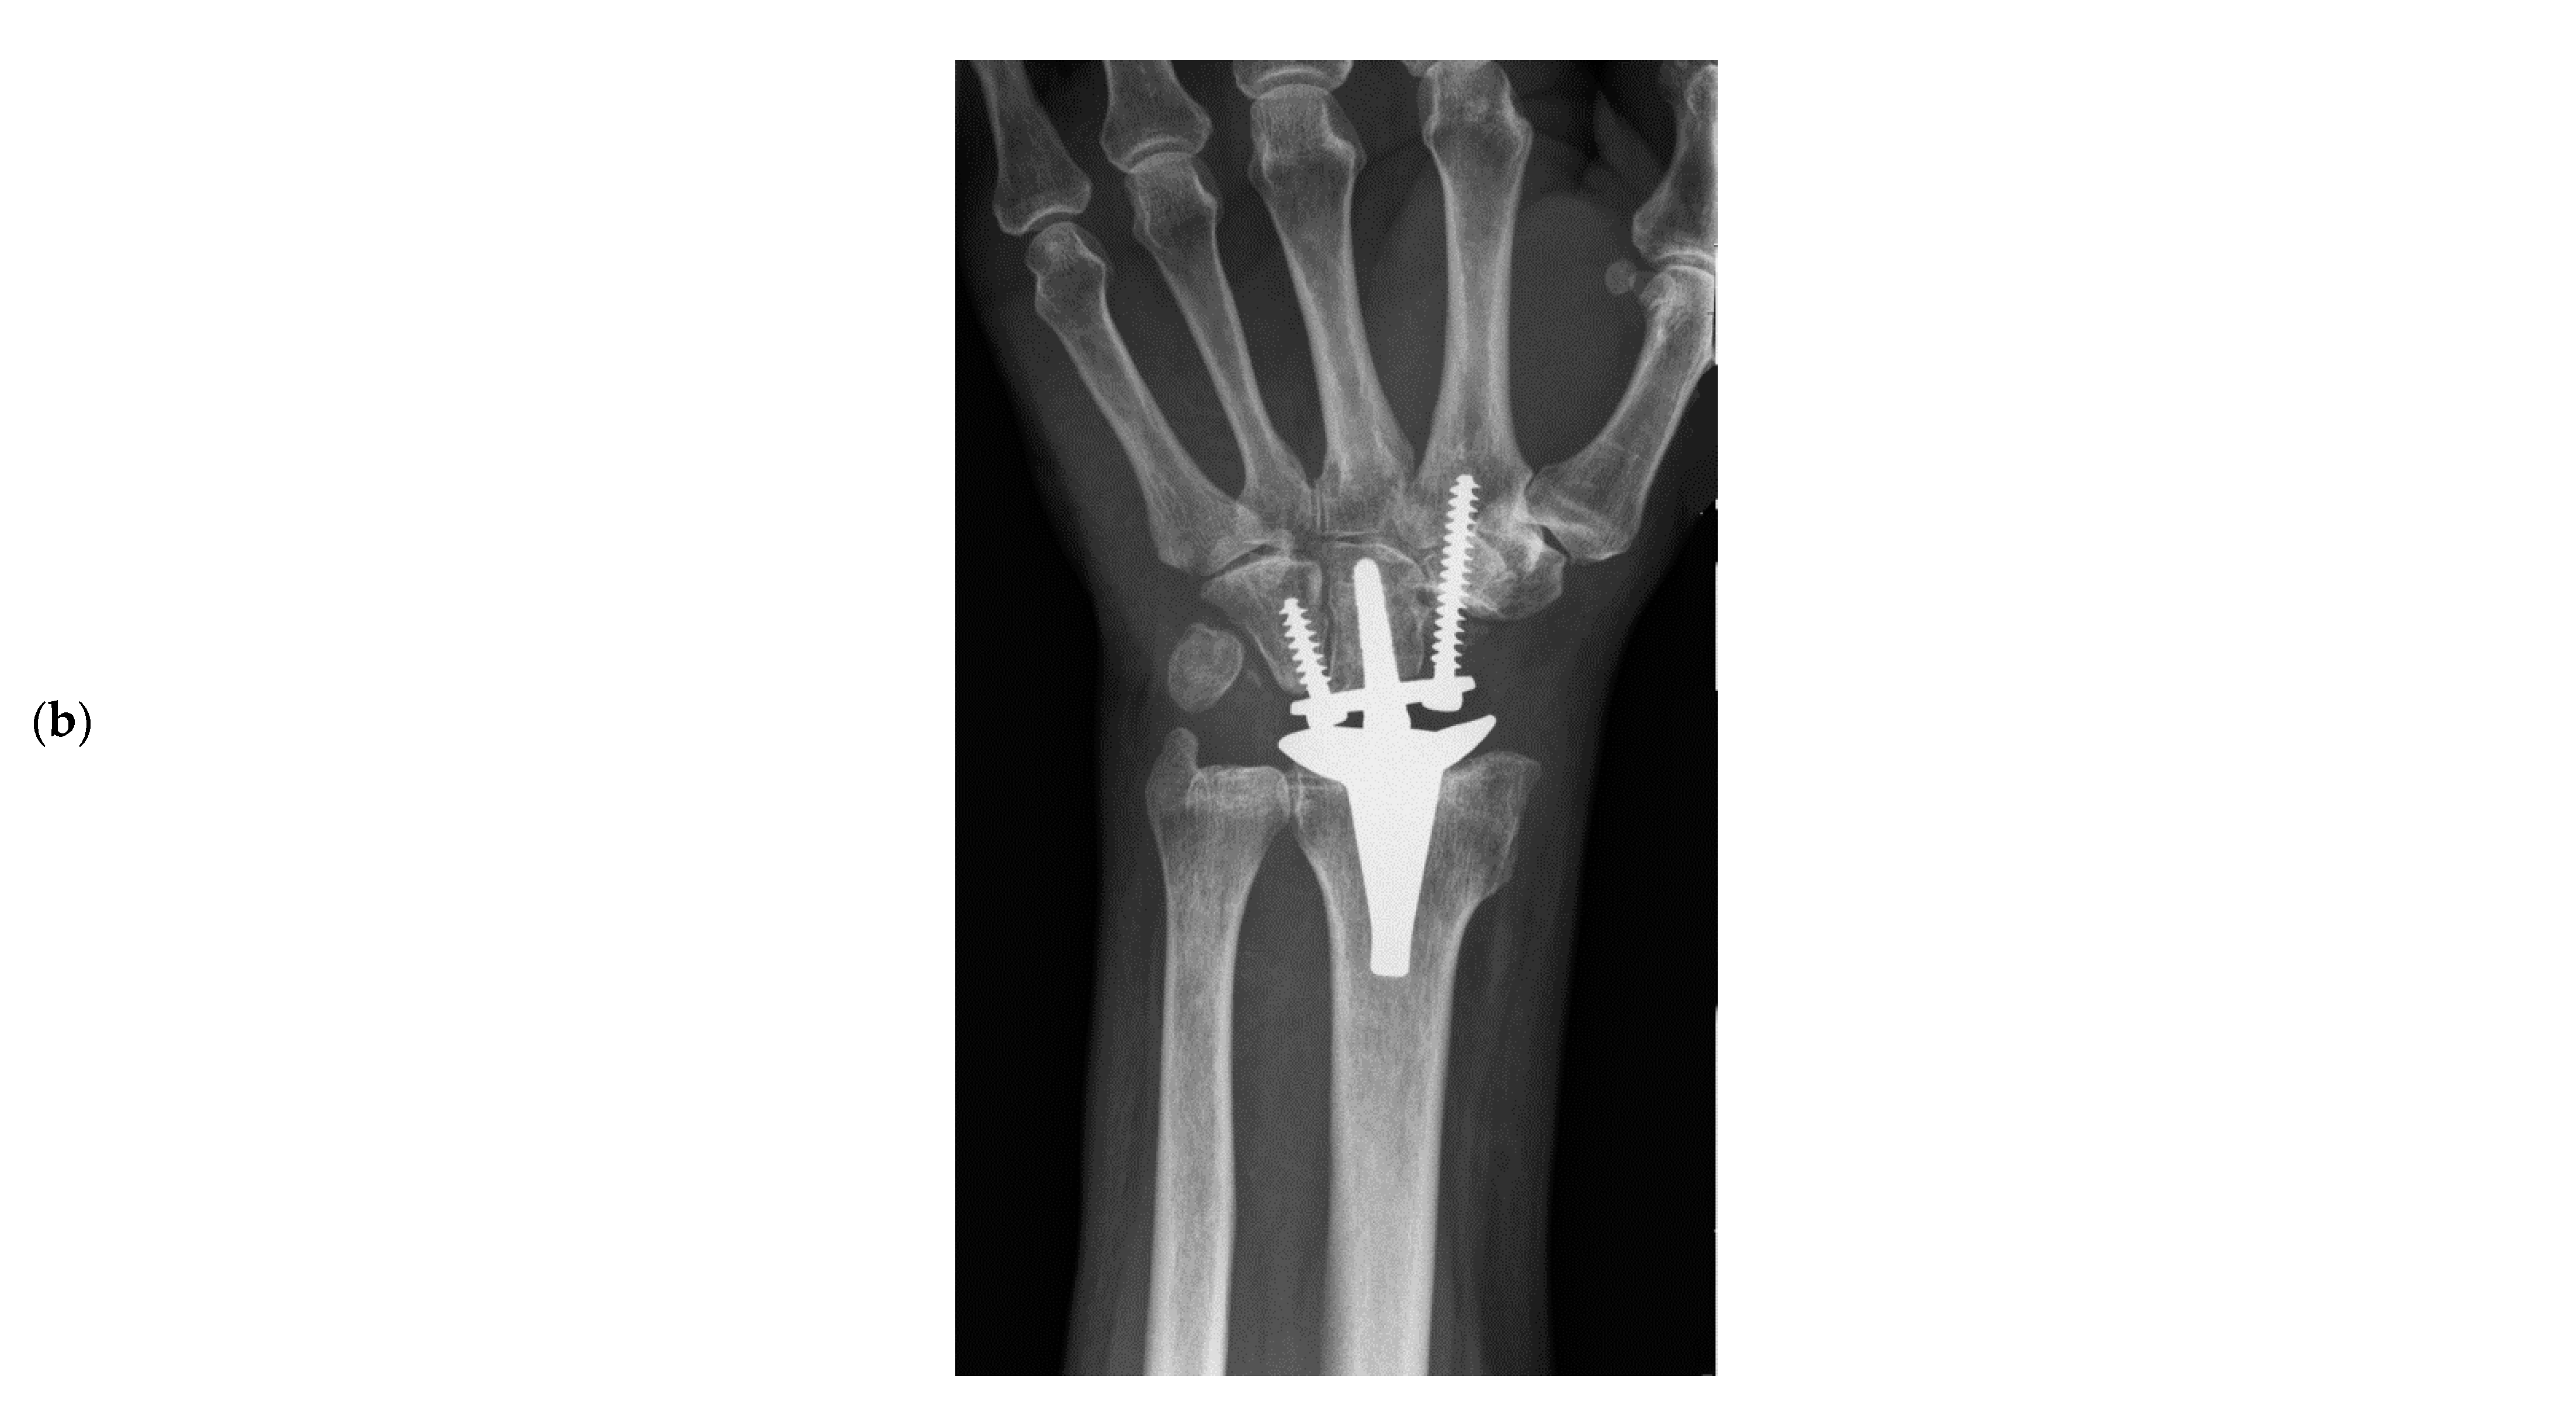

2. Materials and Methods

- Froschauer, S.M.; Holzbauer, M.; Hager, D.; Kwasny, O.; Duscher, D. Proximal Row Carpectomy with Total Scapoidectomy vs. Conventional Carpal Resection for ReMotion Total Wrist Arthroplasty. J. Clin. Med. 2021, 10, 1865. [Google Scholar] [CrossRef] [PubMed]